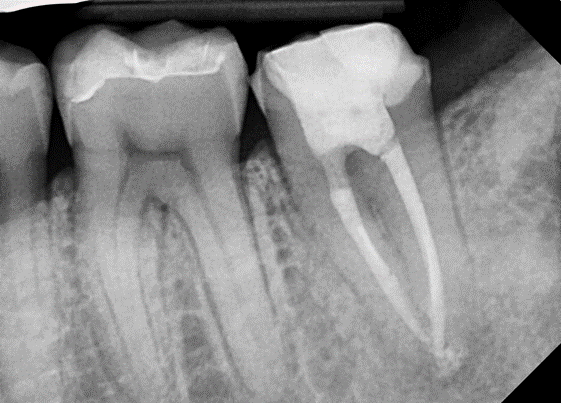

제가 근래에 만난 C형근관을 소개합니다.

![[신경치료] 아래 어금니를 신경치료 할 때 치료할 때 알아야 할 것 (C형근관,고난이도치료) 관련 이미지 8](https://pub-9f2bb3498faf4d1d8714b41df24753e3.r2.dev/content/clinics/archive/nqmm0udu86/naver_blog/honeybeevuvu/assets/by_hash/fcd3afb7ba669bd9ca78c8bc82ee37b3cad75895d59099a1bcd31c0deeb7b1a1.png)

본원의 C형 근관 치료 예시 -20대 여성